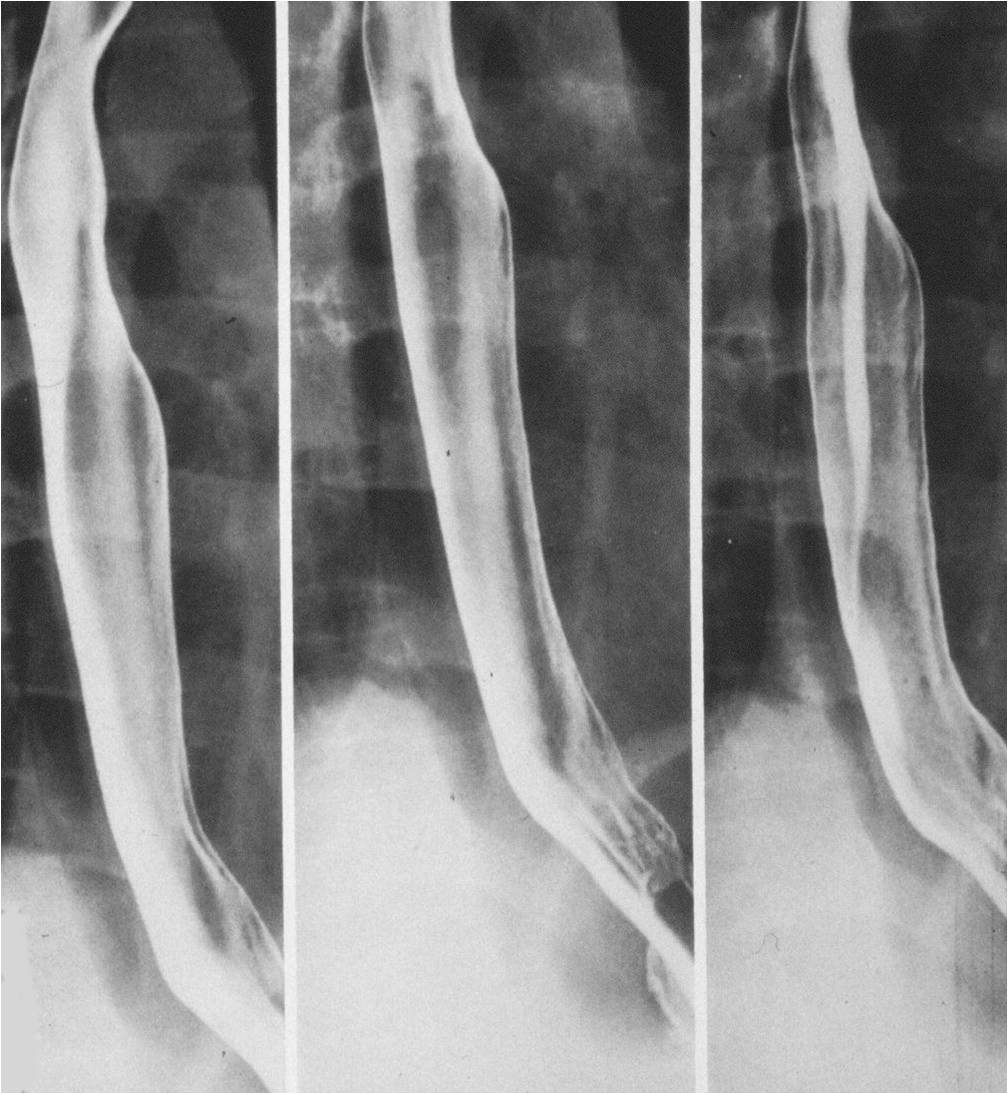

Image

Fig.1.: Normal anatomy of the esophagus

In the double-contrast esophagram the negative contrast is generated by indigestion of CO2 producing crystals. Orientation of the mucosal folds is longitudinal. The luminal diameter is 2-3 cm.